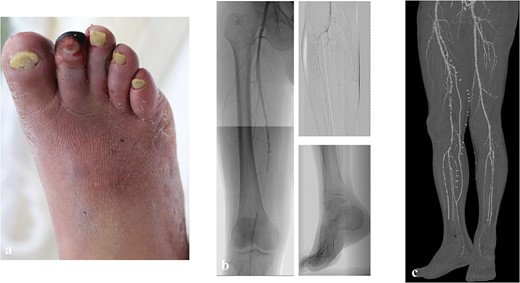

After surgery, remnant infection became exacerbated and spread to the third and fourth digits, and the plantar midfoot (Fig. 2a). Additional amputation and drainage were performed to control the infection, resulting in transection at the Chopart joint (Fig. 2b). Then, the modified Pirogoff technique was applied to achieve wound healing. After starting weight-free walking 1 month after surgery, it took 4 months for the wound to heal and 8 months for bone union (Fig. 2c and d). Ten months later, the patient could walk to the hospital with a cane and did not need a prosthesis at home.

The postoperative clinical picture of case 1; (a) the infection spread to the third, fourth digits, and plantar side; (b) the clinical picture of after transection at the Chopart joint; (c) the clinical picture after Pirogoff amputation; (d) lateral radiography after Pirogoff amputation.